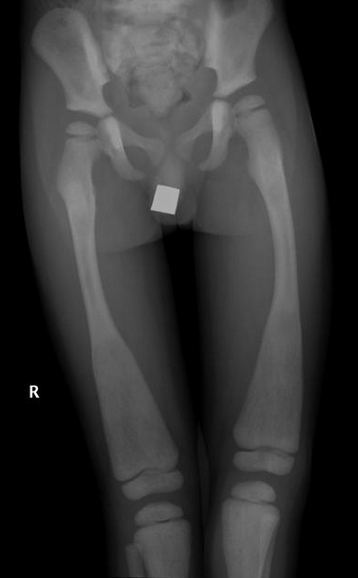

Sickle Cell

• Bone infarcts